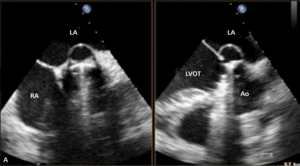

Rycina 2. Tętniak rzekomy lewej komory (strzałki) u pacjentki po implantacji protezy 2-dyskowej w pozycję mitralną.

Tętniaki rzekome lewej komory serca (left ventricular pseudoaneurysm, LVPA) są rzadkim, lecz bardzo poważnym powikłaniem zarówno zawału mięśnia sercowego, jak i leczenia operacyjnego. W tym drugim przypadku szczególnie wymiana zastawki mitralnej jest kojarzona ze zwiększoną częstością występowania LVPA. Pierwszy raz powikłanie to opisano w 1967 r. [11]. Częstość występowania tętniaków rzekomych u chorych po MVR szacuje się na 0,8-2% [12, 13]. Mają inną lokalizację niż tętniaki pozawałowe – LVPA po wymianie zastawki mitralnej stwierdza się zwykle w okolicy podpierścieniowej [14]. Do pęknięcia ściany lewej komory dojść może jeszcze na sali operacyjnej (tzw. wczesne pęknięcie), po kilku dniach (pęknięcie opóźnione), jak i później – po tygodniach lub miesiącach od operacji. Szacuje się, że późne pęknięcia odpowiadają za powstawanie około 10% wszystkich tętniaków rzekomych lewej komory serca po MVR [15]. Powstawaniu wczesnych LVPA sprzyja współistnienie trzech czynników: osłabiona struktura mięśniówki, agresywne manipulacje chirurgiczne i występowanie znacznych sił prowokujących przerwanie ciągłości mięśnia [16]. Jeżeli jama tętniaka jest wystarczająco duża (ryc. 2A, B), to mogą rozwinąć się objawy kliniczne zbliżone do obserwowanych w niedomykalności zastawki mitralnej. Rokowanie jest jednak określone przede wszystkim przez naturę tętniaka. Ograniczona jedynie osierdziem jama LVPA z dużym prawdopodobieństwem (szacowanym na około 45%) może pęknąć [17], co może mieć fatalne konsekwencje. Tętniaka rzekomego różnicować należy z przeciekiem okołozastawkowym, dysfunkcją protezy i przeciekiem między lewą komorą serca a zatoką wieńcową. Leczeniem z wyboru jest naprawa chirurgiczna. W zależności od lokalizacji tętniaka [18] może być ona wykonana z dostępu przez lewy przedsionek (typ 1 LVPA w tylnej części bruzdy przedsionkowo-komorowej) lub od strony epikardium, bez otwierania jam serca (tętniak ograniczony do miokardium [typ 2], powstały wskutek pęknięcia ściany tylnej u podstawy mięśnia brodawkowatego, oraz typ 3 LVPA, do powstania którego dochodzi w wyniku pęknięcia w lokalizacji między typem 1 i 2, czasami możliwy jest dostęp z lewej torakotomii). W przypadku tętniaka rzekomego o wąskiej szyi możliwe jest zamknięcie przezskórne [19].